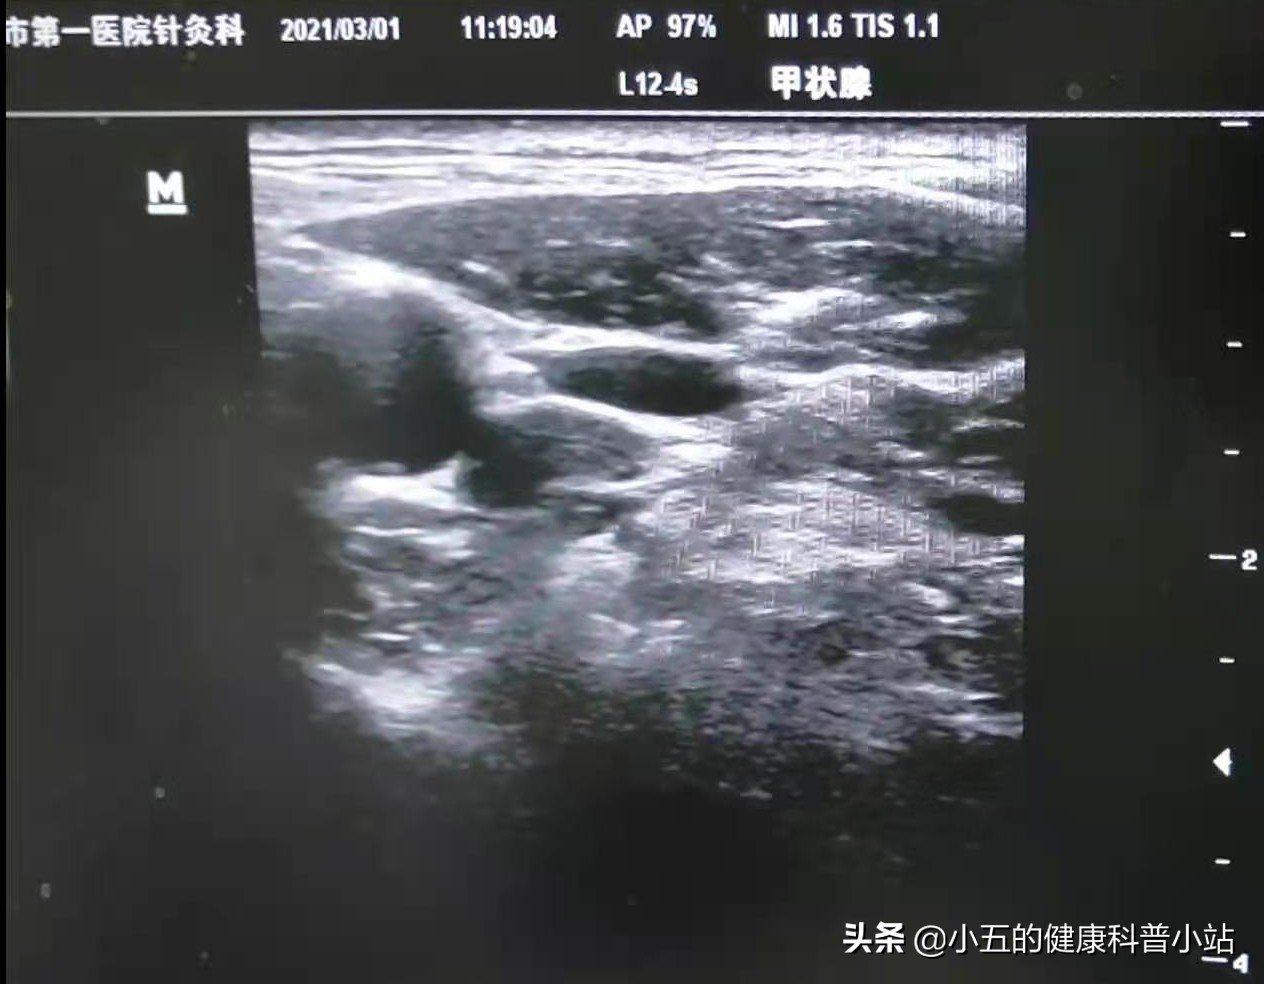

②超声引导下星状神经节阻滞术

在超声引导下将少量、低浓度的局麻药安全地注射于颈部的交感神经节,可有效抑制交感神经兴奋,从而使面部血管扩张,改善面部供血,患者术后可出现面红、发热、眼部充血、眼睑下垂等反应,持续约20分钟,是亨特综合征急性期和康复期改善面部功能,加快神经康复,减轻头晕呕吐的有效手段。